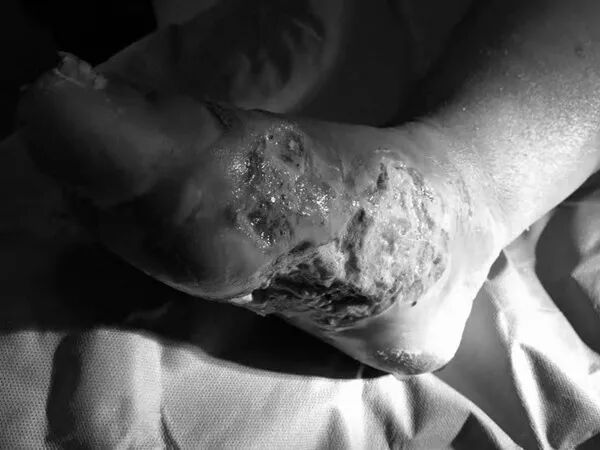

接诊的医生王欣宇打开包扎的敷料,一股恶臭直冲天灵盖,“整个楼道都是臭的”,只见红姐的伤口溃烂面积已从足底蔓延到足背,约15×6厘米,有成年人手掌那么大,流着脓,右脚5个趾头也都红肿,有的已经开始破溃化脓。

照片已做黑白处理